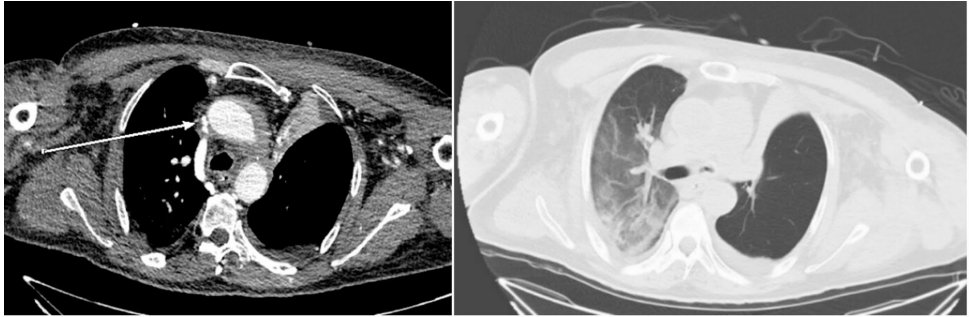

ECMO期间增强CT证实导管尖端对应位置SVC狭窄(图2/4)

通过对比术前/术中CT,首次捕捉到ECMO导管加剧SVC成角至功能性狭窄的动态过程。三维曲面重建(CPR)技术直观显示导管与血管壁的机械性冲突。